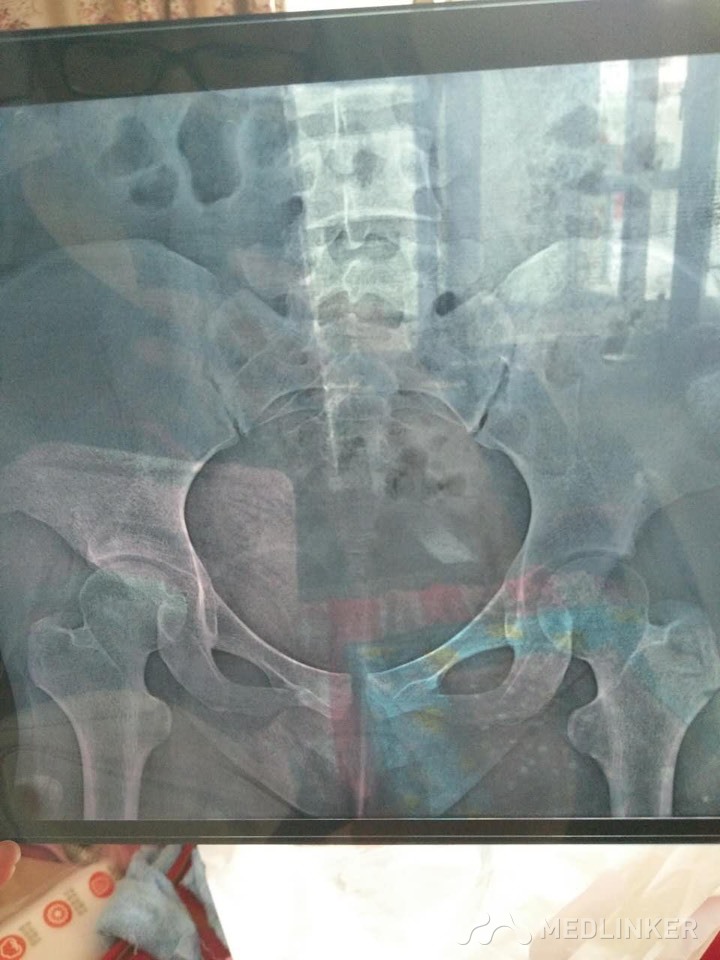

各位同仁帮忙看下这张片子